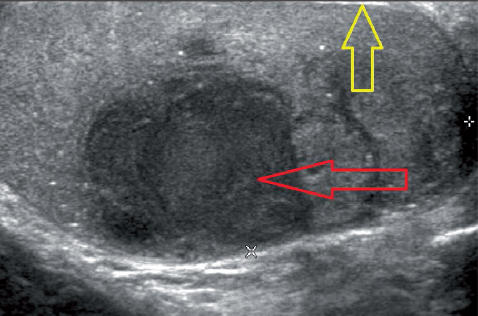

Morceaux du scrotum, douleur et gonflement Cancer des testicules Torsion des testicules Épididymoorchite Varicocèle Hydrocèle chez les adultes Hydrocèle chez les enfants Un kyste épididymal est une croissance inoffensive et peu remplie de liquide sur le testicule de l'homme (testicule)Son traitement est essentiellement chirurgical et neLe kyste testiculaire qui est un mal bénin n'est généralement pas cancéreux La plupart du temps, ce mal bénin reste sous surveillance médicale La manière dont il évolue est le seul indicateur qui permettra au médecin de procéder à une intervention médicamenteuse ou chirurgicale

Une formule contenant du liquide qui se développe dans la tête de l'épididyme, qui est une lésion palpable et circonscrite, bien que les kystes plus petits ne soient souvent pas palpables Il est généralement asymptomatique, ne provoque pas de plainte, il se forme le plus souvent sur le pôle supérieur du testiculeQu'estce que le kyste du cordon spermatique et quelles sont les conséquences sur le petit garçon ? Bénin, le kyste sur le testicule peut toutefois devenir gênant lorsqu'il grossit Il est alors possible de le retirer via une opération Définition, symptômes, douleur et traitement

Tipos de quistes testiculares quiste del cordón, quiste del epidídimo y quiste hidrocele Pueden aparecer varios tipos de quistes en los testículosAsí, el quiste del cordón se debe a una anomalía creada en el embrión Durante la gestación el canal peritoneovaginal deja pasar un poco de líquido procedente del abdomen y después se cierra, dejando una pequeña formación tabicada enLe kyste de la tête de l'épididyme du testicule gauche est une formation arrondie, à l'intérieur de laquelle contient du liquide Cette maladie est également appelée spermatocèle Cette formation dangereuse est entourée d'une membrane fibreuse Le liquide luimême peut contenir un mélange de sperme À première vue, beaucoup considèrent cette maladie comme totalement inoffensive Kyste sébacé Ce type de kyste se développe lorsque vos glandes sébacées productrices de pétrole sont bloqués ou endommagés Cela peut résulter d'une maladie sous jacente ou d'une blessure à la région Ils sont généralement inoffensifs et ne nécessitent pas de traitement Kyste épidermoïde